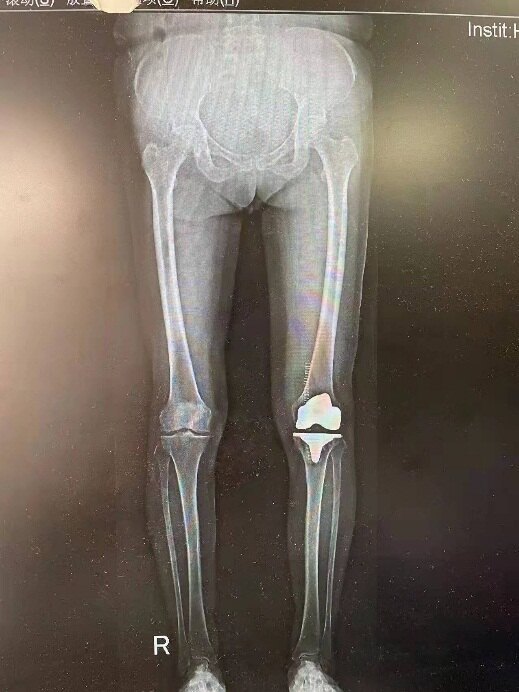

王婆婆今年68歲,飽受左膝關(guān)節(jié)疼痛折磨多年,近兩年來疼痛癥狀明顯加重,接受了鎮(zhèn)痛藥物、理療和關(guān)節(jié)腔內(nèi)注射藥物等治療,效果均不理想,還曾于外院行“保膝手術(shù)”和“干細胞治療”,但是效果差,現(xiàn)在不僅爬坡上坎膝關(guān)節(jié)疼痛難忍,連平路行走都難以超過100米,生活質(zhì)量受到嚴重影響,由于行動受限,外出、社交基本不可能,生理上的疾病導致心理和情緒都受到極大影響。家人看在眼里,急在心上,到處尋找創(chuàng)傷小、效果好的治療方法。 王婆婆和家人看了好幾家醫(yī)院,醫(yī)生都告訴她需要“換關(guān)節(jié)”,婆婆平時跳廣場舞的鄰居也有換了關(guān)節(jié)的,在婆婆看來,手術(shù)還是挺有用的,術(shù)后走路啊,日常活動啊都不錯,但總擔心上下樓的時候,還是趕不上健康的腿,婆婆總想,聽醫(yī)生說,是因為現(xiàn)在的關(guān)節(jié)材料和天生的膝關(guān)節(jié)并不完全一樣,難以完全模擬正常膝關(guān)節(jié)的活動軌跡。 傳統(tǒng)的全膝關(guān)節(jié)置換手術(shù)需要切除前后兩條交叉韌帶,而后交叉韌帶作為膝關(guān)節(jié)最重要的后方及橫向穩(wěn)定裝置,在膝關(guān)節(jié)屈伸活動、負重站立和行走等日?;顒又邪l(fā)揮著非常重要的作用;另外后交叉韌帶具有本體感覺,它被切除后,本體感覺變差,在上下樓梯時更加明顯。 四川大學華西醫(yī)院骨科沈彬教授在西南地區(qū)率先開展了保留后叉韌帶旋轉(zhuǎn)平臺全膝關(guān)節(jié)置換術(shù)臨床研究項目。這一新技術(shù)與傳統(tǒng)全膝關(guān)節(jié)置換術(shù)相比,只切除前交叉韌帶,而完整保留后交叉韌帶,膝關(guān)節(jié)結(jié)構(gòu)上更符合生理,更接近自然膝,更容易恢復膝關(guān)節(jié)正常的運動學軌跡,活動度更好。而且由于保留了后叉韌帶上的本體感受器,患者上下樓啊,久坐后站起立即邁步行走啊,感覺更好,腿更有勁兒。而且相比較傳統(tǒng)的膝關(guān)節(jié)置換手術(shù),這種新假體、新技術(shù)切除的組織更少,保留的骨頭更多。保留的更多骨質(zhì)也有利于將來翻修。這種新假體在國內(nèi)使用很少,數(shù)據(jù)不多,但是國外有十年以上長期隨訪結(jié)果,從數(shù)據(jù)來看,這種關(guān)節(jié)的使用壽命也更長。沈彬教授在保留后叉韌帶技術(shù)基礎(chǔ)上,還將人工膝關(guān)節(jié)脛骨側(cè)組件由傳統(tǒng)的固定平臺升級為旋轉(zhuǎn)平臺,匹配度更高,患者體驗更好。 在了解到華西醫(yī)院開展的這項新術(shù)式后,王婆婆一家立即前往華西醫(yī)院就診,沈彬教授對王婆婆進行了全面的評估:跛行步態(tài),左膝疼痛嚴重,活動受限伴有屈曲內(nèi)翻畸形;X線片顯示關(guān)節(jié)間隙狹窄,呈“骨磨骨”表現(xiàn),膝關(guān)節(jié)周圍骨贅形成;骨關(guān)節(jié)炎已經(jīng)到達終末期,只有通過手術(shù)治療才能解決患者的病痛。手術(shù)之后婆婆左膝關(guān)節(jié)畸形得到完全糾正,膝關(guān)節(jié)活動度非常好。術(shù)后X線片顯示假體與骨完美匹配,固定良好,位置正常。術(shù)后2周婆婆來院復查時,已經(jīng)棄拐行走,并可以自由下蹲和坐矮板凳了,困擾X婆婆多年的膝蓋問題終于得到圓滿解決。